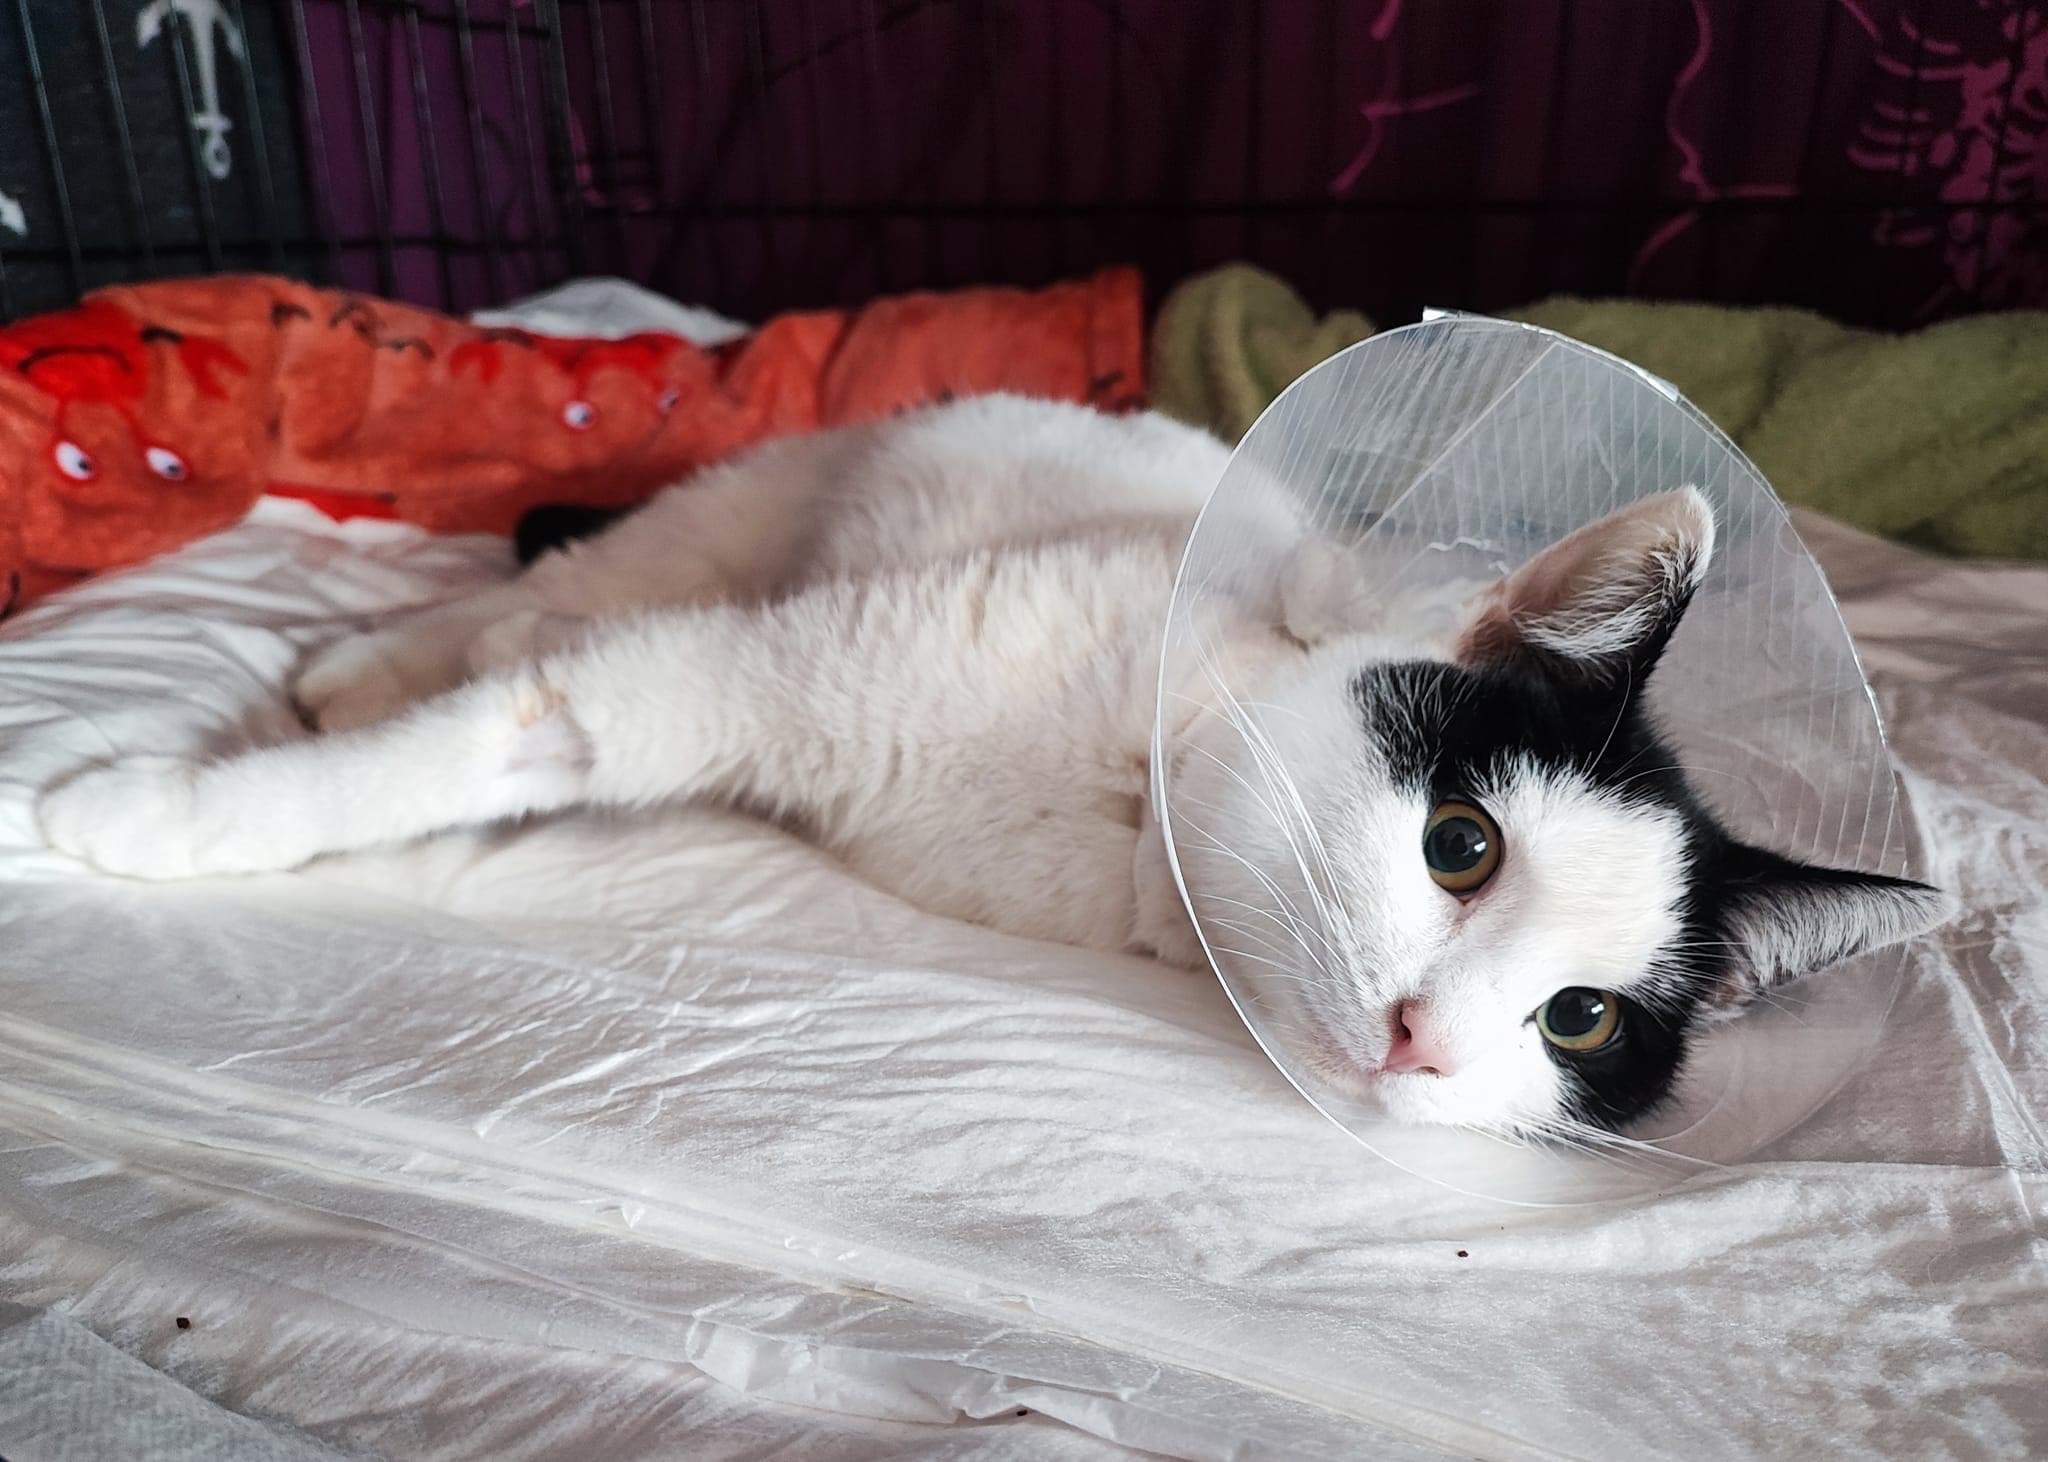

03.04.2023: Heute war unsere Lucy wieder beim Tierarzt. Es wurden die Fäden gezogen. Ein paar Tage muss sie noch ihren Trichter tragen, dann darf er entfernt werden. Ein Blutbild wurde heute auch wieder gemacht. Ihre Werte werden immer besser. Eines ihrer Beinchen macht uns noch ein wenig Sorgen. Damit tritt sie nicht richtig auf. Sie versucht es aber immer wieder. Sie geht selbstständig auf die Toilette und brauchte keine Inkontinenzunterlagen mehr.

30.04.2023: Der Termin für Lucy´s zweite OP steht jetzt fest. Am kommenden Mittwoch ist es soweit. Es wird dann ihr rechtes Hüftgelenk operiert. Die Tierärzte aus Berlin haben uns gesagt, dass sie darauf hoffen, das sich das Gelenk eventuell mit Bindegewebe festigen wird. Dem ist aber leider nicht so. Letzte Woche wurde ein neues Röntgenbild gemacht und da sieht man eindeutig, dass eine zweite OP notwendig ist.